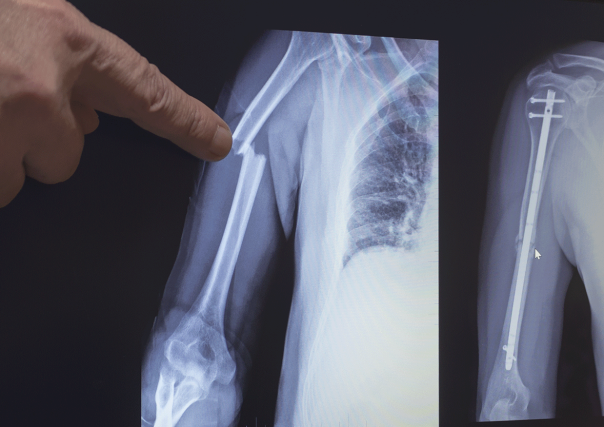

Gebrochener Arm

Beim chirurgischen Eingriff wird ein Loch in den Markraum eines gebrochenen Knochens gebohrt und ein langer intermedullärer Titan-Nagel in das Loch eingeführt. Der Nagel wird dann zum Zusammenhalt der gebrochenen Knochenstücke verschraubt, um erfolgreiche Heilung zu gewährleisten.

Im Vergleich mit anderen Medizinprodukten sehen IM-Nägel nicht ausserordentlich komplex aus, sind aber sehr schwierig herzustellen. Da sie in Knochen eingeführt werden, müssen sie absolute präzise anatomische Biegungen aufweisen. Als Hilfestellung für den Chirurgen können sie weitere Merkmale umfassen, die weniger Drehungen und Drehmoment im Verlauf des operativen Einsatzes erfordern.

Für zehn Patienten mit Schienbeinbruch können zehn unterschiedlich grosse IM-Nägel benötigt werden. Das bedeutet, dass wir viele verschiedene Grössen in unterschiedlichen Mengen herstellen. Jede Grösse erfordert eine bestimmte, auf den Knochen einer Person präzise zugeschnittene Biegung. Wie bei allen medizinischen Implantaten muss jeder IM-Nagel strenge Qualitätsstandards erfüllen.